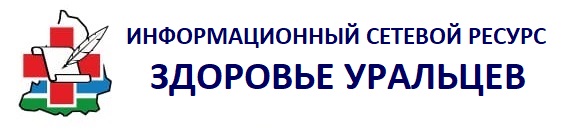

Рентгенэндоваскулярные хирурги Городской больницы Каменска-Уральского впервые в своей практике выполнили тромбоэкстракцию — удаление тромбов из сосудов головного мозга с помощью малотравматичной методики. Технология позволила вернуть к нормальной жизни уже трёх пациентов, в том числе 74-летнего мужчину, который из-за перенесённого ишемического инсульта был частично парализован и не мог говорить. Высокотехнологичное вмешательство помогло восстановить функции организма.

«Пациент 74 лет поступил к нам с полным параличом правой стороны тела, нарушением движения глазных яблок, отсутствием речи. Мужчину осмотрел невролог, с помощью компьютерной томографии были выявлены в одном сосуде две закупорки по 3 миллиметра. Мы провели тромболизис и сразу же начали тромбоэкстракцию через ангиограф. Оба тромба были удалены, физические функции мужчины начали восстанавливаться в этот же день», — рассказал заведующий отделением рентгенохирургических методов диагностики и лечения Городской больницы Каменска-Уральского Кобилжон Джураев.

Хирург объясняет, что сейчас у пациентов, перенёсших инсульт, гораздо больше шансов на выздоровление, так как тромболизис может растворять только небольшие закупорки и только в первые 4,5 часа с начала характерных симптомов. Тромбоэкстракция позволяет справляться с более крупными сгустками, в том числе, когда невозможно установить время начала сосудистой катастрофы.

Малотравматичные операции проводятся под местной анестезией и занимают в среднем около получаса. Хирурги через бедренную артерию микрокатетером доходят до места закупорки в сосуде головного мозга, захватывают тромб и вытягивают его из артерии. После удаления сгустка кровоснабжение приходит в норму, а жизненно важные функции пациента восстанавливаются.